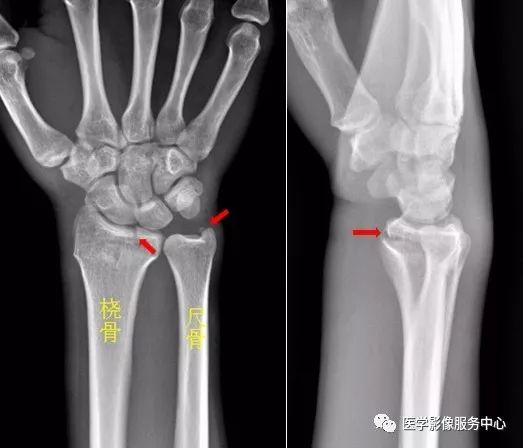

右侧桡骨远端可见不规则透亮骨折线,并累及关节面。右侧桡骨远端骨折尺骨茎突见游离骨碎片影。右侧尺骨茎突骨折。肘关节

左侧尺骨上段见骨折透亮线,断端稍移位成角。左侧尺骨上段青枝骨折。

Warmreminder: 青枝骨折多见于儿童,由于骨皮质韧性好,受伤时不易看出,若发现可疑骨折征象。

小妙招 嘱家属过一周~两周再复查,若是骨折,可见新生骨生长。(此患者就是踝关节扭伤,踝关节正侧位未见异常,加拍足正位时发现外踝骨折)